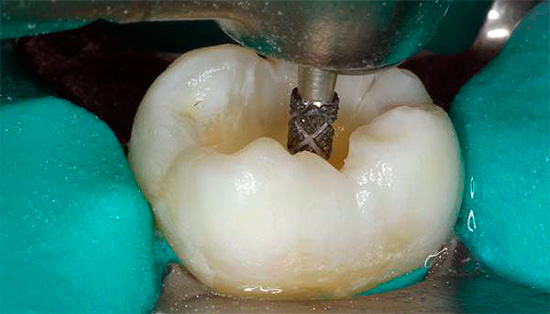

- apertura di un buon accesso alle bocche dei tre canali;

- estensione della bocca;

- Sovrapposizione di Cofferdam

- estirpazione (estrazione) della polpa da tutti e tre i canali mediante estrattori di polpa;

Un microscopio in endodonzia viene utilizzato, in particolare, per diagnosticare il numero di canali radicolari e la qualità del loro passaggio. Il trattamento della pulpite di un dente a tre radici al microscopio consente di trovare e trattare rapidamente anche i passaggi più difficili e ci sono molti casi simili nella pratica di un dentista.

Un microscopio endodontico ci consente di dire con quasi il 100% di certezza alla fine del trattamento che tutti i canali sono stati passati e correttamente sigillati. È lui che ti consente di controllare ogni fase del trattamento della pulite, prevenendo ulteriori complicazioni. Il trattamento tradizionale senza l'uso di un microscopio è spesso associato alla presenza di conseguenze negative a lungo termine, ad esempio a causa del fatto che il medico semplicemente non ha potuto vedere il canale aggiuntivo nel dente e lo ha perso durante il trattamento, lasciando una polpa infetta al suo interno.